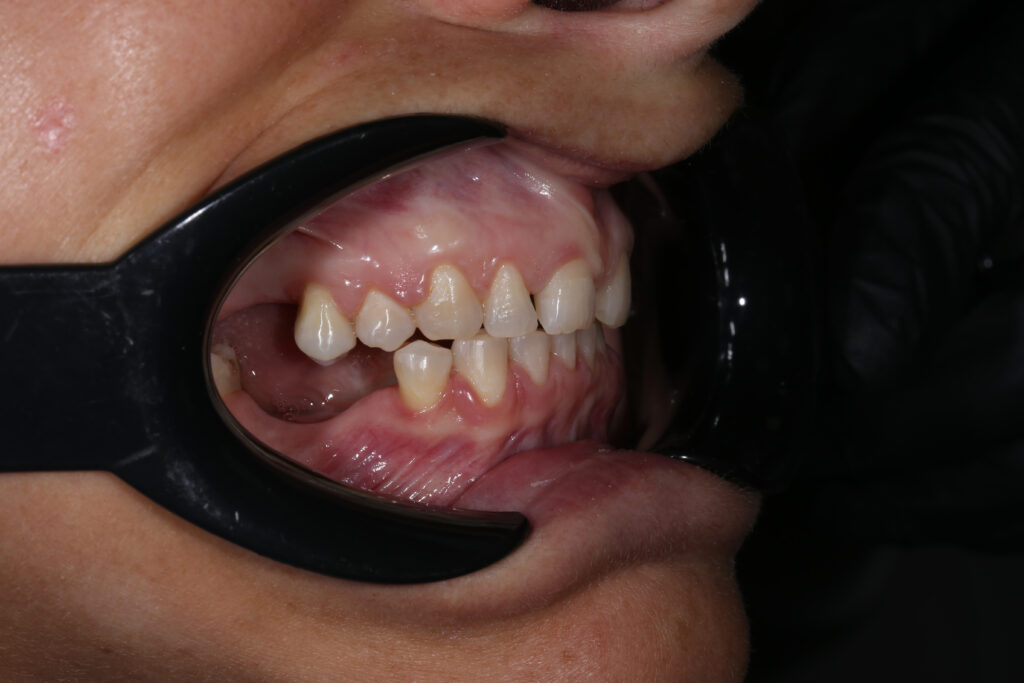

Ситуация до лечения

Пациентка 39 лет была направлена стоматологом-ортопедом для ортодонтической подготовки перед протезированием.

Из-за множественных давних удалений жевательных зубов, произошла деформация зубных рядов, зубы разъехались в область удаленных, что затрудняло протезирование в момент обращения к ортопеду.

Так же можно отметить сильное снижение высоты прикуса (верхние зубы на 100% перекрывали нижние, что вызывало хроническую травму десны), а также повышенную стираемость твердых тканей зубов,

что является следствием повышенной нагрузки, которую много лет испытывали передние зубы, в связи с отсутствием жевательных зубов.

пациент до брекетов